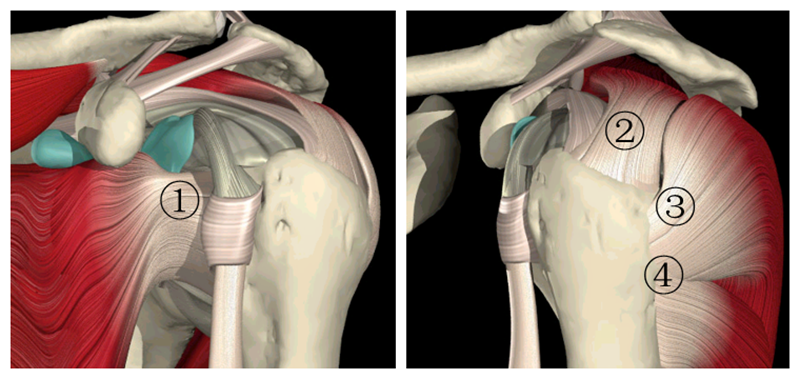

肩关节解剖结构

肩袖是由冈上肌、冈下肌、肩胛下肌及小圆肌的腱性部分组成的鞘状结构。它包绕盂肱关节、肱骨头、关节囊,形成近似袖套样肌样结构,具有保持肱盂关节稳定,维持上臂各种姿势和完成各种运动的功能。

图1肩关节骨解剖 1.锁骨2.肩胛骨3.肩峰4.喙突5.肱骨头6.关节盂

图2 肩袖解剖1.肩胛下肌2.冈上肌3.冈下肌4.小圆肌